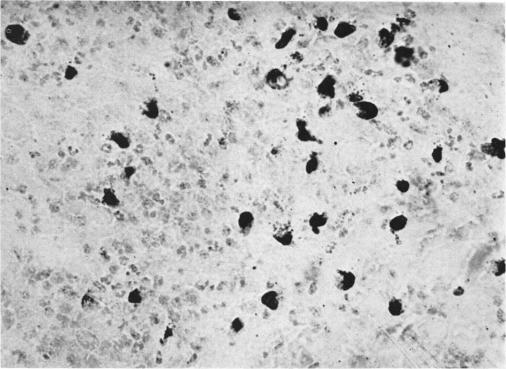

To study the zonal response to antigenic stimuli in lymph nodes of the cat, three groups of eight cats received epicutaneous application of oxazolone and inoculations of ovalbumin plus Freund's adjuvant and feline leukaemia virus (FeLV) respectively into the left hind footpads. The changes in the left popliteal nodes were followed histologically and autoradiographically for 14 days. In the oxazolone-treated group, there was an extremely marked proliferation of blast cells in the paracortical areas, maximal on days 3–7; germinal centres developed on day 6; plasma cells did not feature in the response. In the ovalbumin-treated group, the nodes developed a full zonal response, with marked blast cell response in the paracortical areas, formation of prominent germinal centres and a striking plasma cell reaction. In both groups, there was a considerable increase in mast cell numbers in the course of the reactions; the origin of the new mast cells was not clear. The response to FeLV was minimal, despite direct stimulation of the node with high titre virus.

为研究猫淋巴结对抗原刺激的区域反应,三组各八只猫分别接受了恶唑酮的表皮应用,并将卵清蛋白加弗氏佐剂和猫白血病病毒(FeLV)分别接种到左后足垫。对左侧腘窝淋巴结的变化进行了14天的组织学和放射自显影观察。在恶唑酮治疗组中,皮质旁区域的母细胞极度显著增殖,在第3 - 7天达到最大值;生发中心在第6天形成;浆细胞未参与该反应。在卵清蛋白治疗组中,淋巴结产生了完整的区域反应,皮质旁区域有明显的母细胞反应,形成突出的生发中心和显著的浆细胞反应。在两组中,反应过程中肥大细胞数量均有相当大的增加;新肥大细胞的来源尚不清楚。尽管用高滴度病毒直接刺激淋巴结,但对FeLV的反应极小。